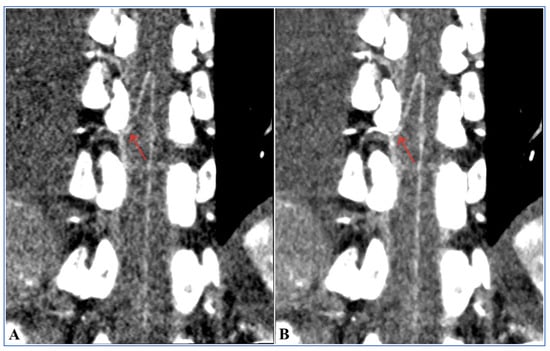

| Groups | Image Reconstruction Methods | Visualization Scores of the Adamkiewicz Arteries | Hairpin Curve | Branching Level | ||||

|---|---|---|---|---|---|---|---|---|

| 1 = Poor | 2 = Fair | 3 = Good | 4 = Fine | 5 = Excellent | ||||

| Group B | 120 kV FBP | 12 (24.0%) | 14 (28.0%) | 11 (22.0%) | 9 (18.0%) | 4 (8.0%) | 38 (76.0%) | 24 (48.0%) |

| Group A | 100 kV FBP | 5 (10.0%) | 9 (18.0%) | 16 (32.0%) | 12 (24.0%) | 8 (16.0%) | 45 (90.0%) | 36 (72.0%) |

| 100 kV ASIR-V 80% | 2 (4.0%) | 3 (6.0%) | 9 (18.0%) | 22 (44.0%) | 14 (28.0%) | 48 (96.0%) | 45 (90.0%) | |

| 100 kV ASIR-V 90% | 2 (4.0%) | 3 (6.0%) | 7 (14.0%) | 24 (48.0%) | 14 (28.0%) | 48 (96.0%) | 45 (90.0%) | |

| 100 kV ASIR-V 100% | 2 (4.0%) | 3 (6.0%) | 6 (12.0%) | 24 (48.0%) | 15 (30.0%) | 48 (96.0%) | 45 (90.0%) | |